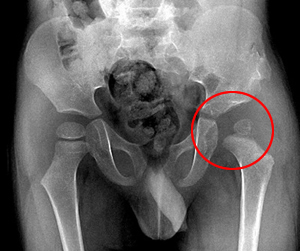

2、骨折线的高度:

骨折线的高度也是外伤性股骨头坏死的病因,骨折线愈靠近股骨头愈高,坏死率愈高。根据骨折线部位可将股骨颈骨折分为头型、头下型、颈中型和基底型。